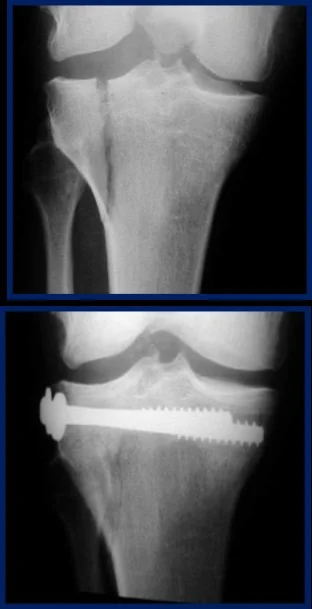

Intra-articular Fractures

- Need perfect anatomical reduction

- To avoid osteoarthritis

- Need early mobilization

- to maintain good range of motion and function

| Screws | Good fixation – stable – Can apply good inter‑fragmentary compression In simple fractures Can be applied percutaneous | ![]() ![]() |